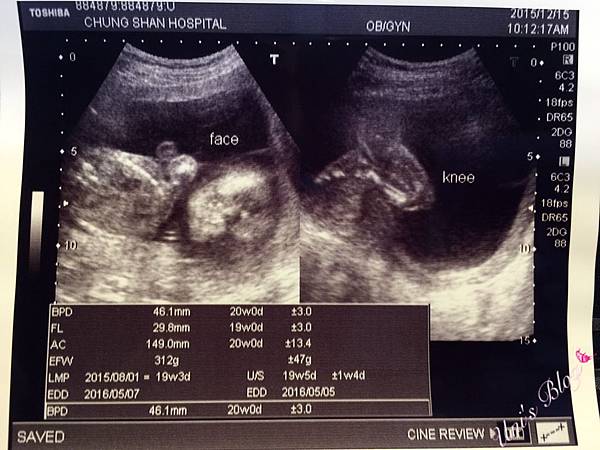

孕媽咪♥20W。羊膜穿刺-中山醫院